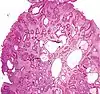

Peutz-Jeghers Polyp All digestive tract Smooth muscle bundles between nonneoplastic epithelium, "Christmas tree" appearance No

Micrograph of a Peutz–Jeghers colonic polyp – a type of hamartomatous polyp. H&E stain.